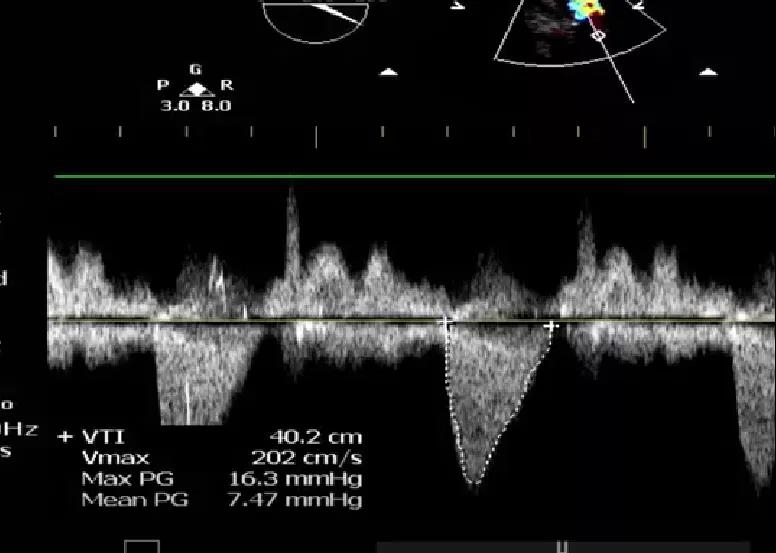

9月27日上午10时,直播开始,魏来教授团队耗时约1小时,经右侧股动脉植入23# Renatus介入主动脉瓣。瓣膜植入位置理想,功能表现出色,造影及经食道超声观察显示瓣膜无中央性返流,轻微瓣周漏,无冠脉血流受阻,无传导阻滞,主动脉瓣峰值流速降至2.0m/s,平均跨瓣压差降至7mm/Hg。手术取得圆满成功。

术后经食道超声